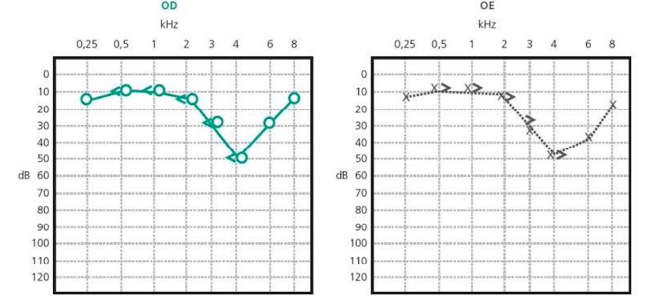

Paciente com 35 anos apresenta perda de audição progressiva associada a zumbidos. Otoscopia dentro da normalidade e audiometria conforme figura a seguir:

Qual o mais provável diagnóstico?